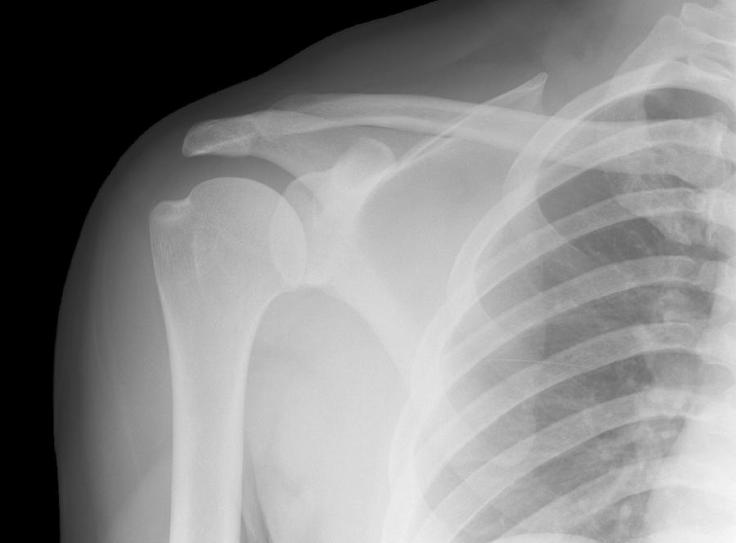

Just when I thought I was moving past my broken collarbone, my shoulder started to seize up and put me back in physical therapy, so I was using my left arm for most things, and then I dislocated a rib doing yard work (tree pruning), because my right arm was useless and I refused to accept that I just couldn’t do the work I wanted to do.

So I can’t ride a bike, because my shoulder is a nest of angry hornets, and now I can’t even run, because it feels like someone put a packing staple in my chest. I tried to run through that pain on Saturday and got rewarded with a handful of ibuprofen with lunch, dinner and breakfast the next day.